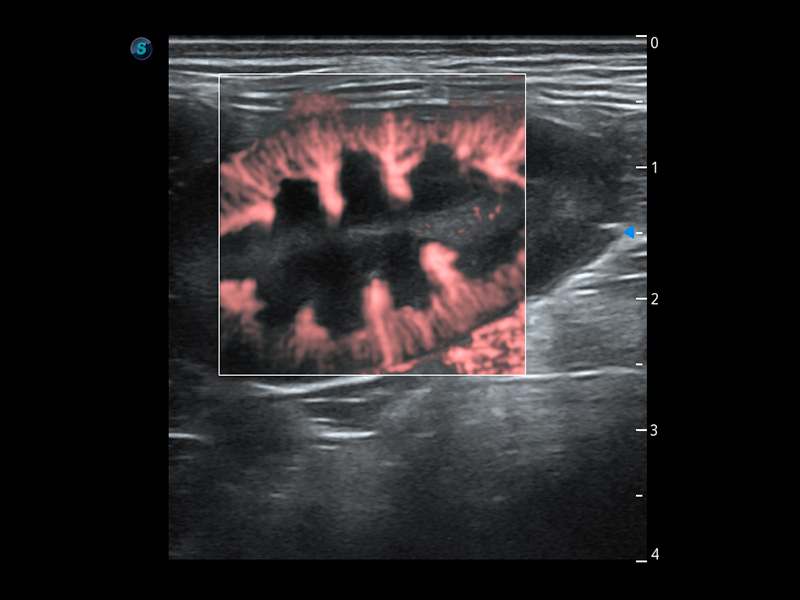

ProPet 60 作为一款高端台式动物超声设备,为动物医生的日常诊断提供了一系列贴合动物临床需求、解决临床实际问题的高级成像功能。凭借全系列高清探头,满足医生对腹部、心脏、生殖、浅表、肌骨等成像的所有需求,切实帮助您提升检查效率,提高诊断信心。

动物是人类最亲密的朋友和最值得信赖的伙伴。银河集团官网也一直致力于探索动物专用的超声影像解决方案。 全新推出的ProPet系列,是银河集团官网在动物超声影像智能化、专业化、精准化的一次跨越式革新。动物不能用言语来表述自己的不适,通过超声影像,ProPet系列搭建了动物医生与不同物种沟通的“桥梁”,为动物医生注入了“治愈之力”。